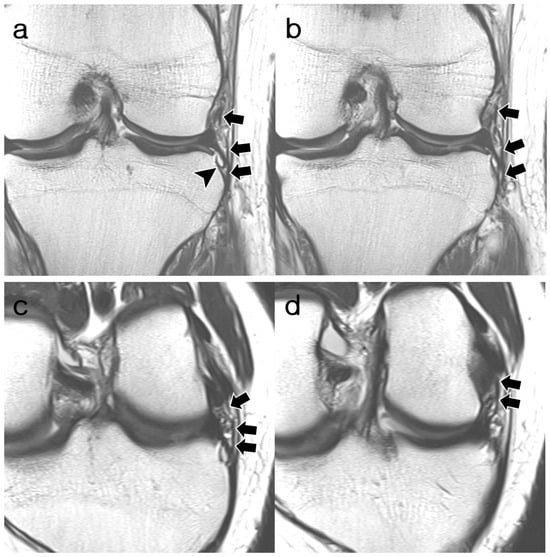

3.2. ALL Visibility

3.3. ALL Morphology